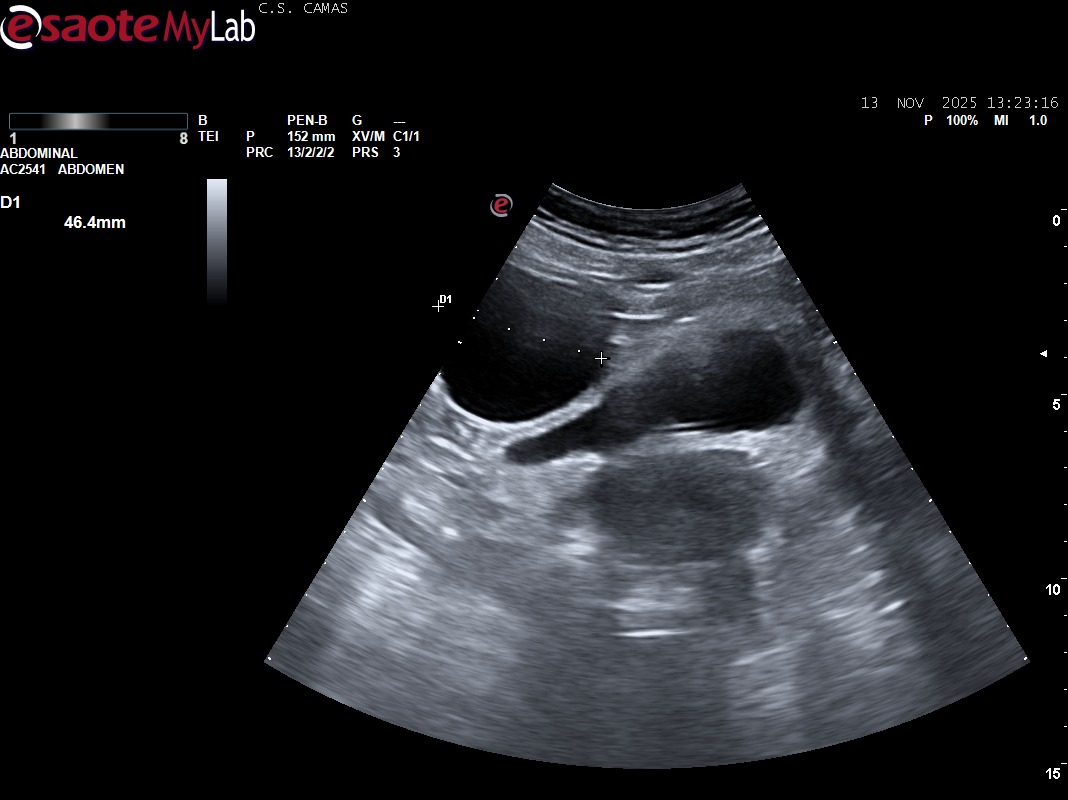

Hallazgos ecográficos

Ecografía clínica (POCUS):

Es importante diferenciar quistes ováricos simples sin ecos internos, como en este caso, de aquellos con ecos en su interior, característicos de quistes hemorrágicos.